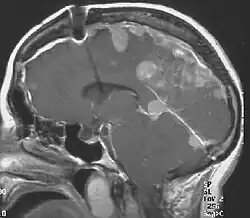

Meningiomas in a person with NFII

The so-called acoustic neuroma of NF2 is in fact a schwannoma of the nervus vestibularis, or vestibular schwannoma. The misnomer of acoustic neuroma is still often used. The vestibular schwannomas grow slowly at the inner entrance of the internal auditory meatus (meatus acousticus internus). They derive from the nerve sheaths of the upper part of the nervus vestibularis in the region between the central and peripheral myelin (Obersteiner-Redlich-Zone) within the area of the porus acousticus, 1 cm from the brainstem.